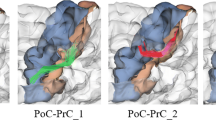

Fiber tracking is the most popular technique for creating white matter connectivity maps from diffusion tensor imaging (DTI). This approach requires a seeding process which is challenging because it is not clear how and where the seeds have to be placed. On the other hand, to enhance the interpretation of fiber maps, segmentation and clustering techniques are applied to organize fibers into anatomical structures. In this paper, we propose a new approach to automatically obtain bundles of fibers grouped into anatomical regions. This method applies an information-theoretic split-and-merge algorithm that considers fractional anisotropy and fiber orientation information to automatically segment white matter into volumes of interest (VOIs) of similar FA and eigenvector orientation. For each VOI, a number of planes and seeds is automatically placed in order to create the fiber bundles. The proposed approach avoids the need for the user to define seeding or selection regions. The whole process requires less than a minute and minimal user interaction. The agreement between the automated and manual approaches has been measured for 10 tracts in a DTI brain atlas and found to be almost perfect (kappa > 0.8) and substantial (kappa > 0.6). This method has also been evaluated on real DTI data considering 5 tracts. Agreement was substantial (kappa > 0.6) in most of the cases.